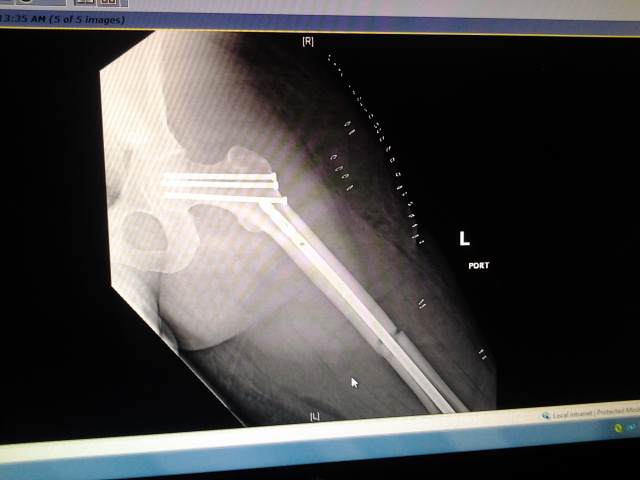

So... To start, I had a motorcycle accident and broke my leg in two places. They had to insert a rod and a bunch of screws in. But I think I had nerve damage. How I know? Well the outside of both my legs to the small toes are numb. Not totally, I have feeling. But they're numb.

I had the accident on 4-7-14. Been non-weight bearing on my left leg since.

Attachment:

2014-04-10 08.07.56.jpg

2014-04-10 08.07.56.jpg [ 91.21 KiB | Viewed 5416 times ]

Just don't ask me how my bike fared :/